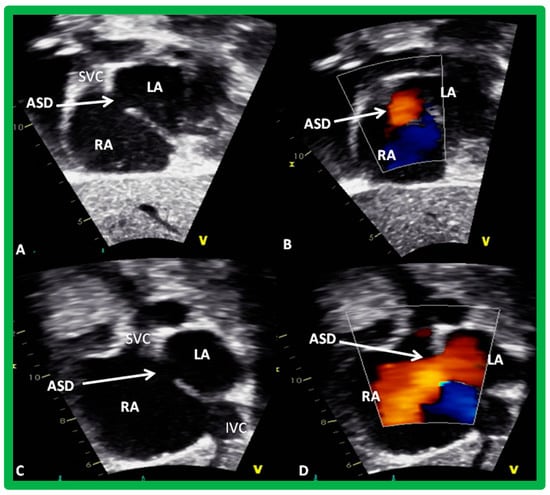

2. Diagnosis

4. Patient Selection for Device Occlusion